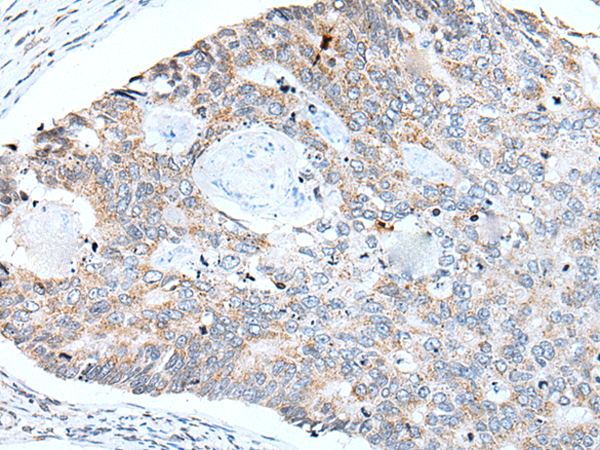

分类: 科研抗体货号: P05945别名: CFND; CFNS; EFB1; EFL3; EPLG2; Elk-L; LERK2应用: IHC反应种属: Human, Mouse, Rat